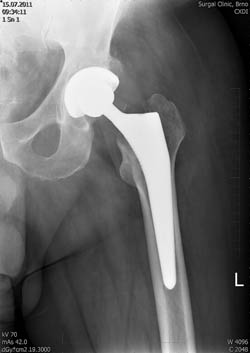

Umělý kloub – aloplastika – totální endoprotéza (TEP)

Aloplastika kyčelního kloubu je náhrada poškozeného kloubu implantátem, kdy nahrazujeme jamku acetabula i hlavici stehenní kosti.

Cementovaná endoprotéza:

- kostním cementem fixovaná polyethylenové jamka

- kostním cementem fixovaný dřík

Hybridní endoprotéza:

- jamka necementovaná – obvykle z titanu

Necementovaná endoprotéza:

- jamka necementovaná

- dřík necementovaný

Do ukotvené jamky je vložena vložka, která tvoří kluzný povrch, na konus dříku nasazujeme hlavičku endoprotézy. Meteriály, které se užívají k výrobě kluzných povrchů, jsou zejm. CrMoCo ocel, polyetylén, keramika a oxinium.